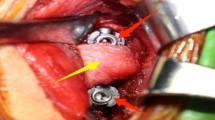

We report three cases of oesophageal complications due to pressure necrosis secondary to screws post anterior plate fixation of the cervical spine. Two of the patients were treated using primary closure; and the third by conservative treatment, which consisted of wound drainage and an external orthotic device application. We recommend the early surgical closure and removal of the metallic implant with debridement as the first option of treatment. In the event that this option is not suitable, we suggest that wound drainage, tube feeding and parenteral antibiotics may be an appropriate alternative.

Hanci, M., Toprak, M., Sanoğlu, A. et al. Oesophageal perforation subsequent to anterior cervical spine screw/plate fixation. Spinal Cord 33, 606–609 (1995). https://doi.org/10.1038/sc.1995.128